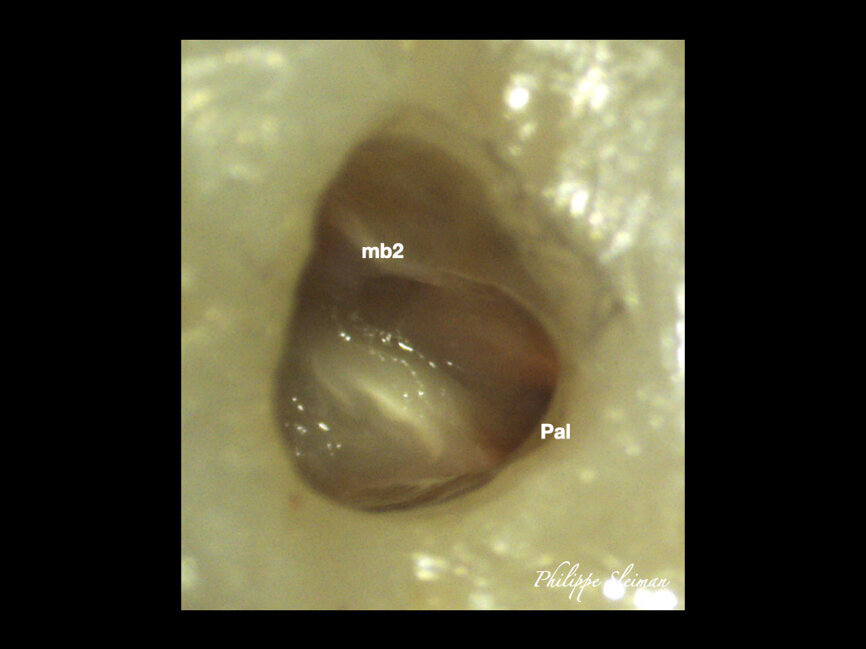

The preoperative radiograph and access cavity under the operating microscope (Images: Philippe Sleiman)

The patient was referred for a root canal therapy of his maxillary molar. Upon creating the access cavity under a clinical microscope, we could see that the entry to the second mesial canal was at a distance from the entrance to the first (Fig. 5). Figure 6 shows the proximity of the second mesiobuccal canal to the palatal canal. Increasingly, second mesial canals are being treated in the maxillary second molar owing to the use of the microscope, ultrasonic instruments and irrigation and of course owing to the clinical knowledge regarding the use of these and owing to the use of CBCT imaging sometimes.